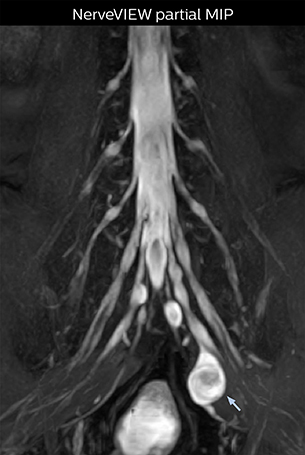

At Northern Fukushima Medical Center in Japan, excellent MRI visualization of nerves helps support confident diagnoses and informs surgical treatment decisions for patients with lower limb symptoms. MRI technologist Tanji and orthopedic surgeon Dr. Yabuki share how direct nerve visualization with the 3D NerveVIEW method adds information when diagnosing atypical herniations. The additional insights changed their way of working and benefit their patient care, as illustrated by some clinical examples.

“In patients with lower extremity neurological symptoms, NerveVIEW helps us to determine the disease matching the patient’s symptoms by directly visualizing the nerves. We use the sequence mainly, when there is suspicion of intraforaminal stenosis, extraforaminal stenosis or lateral disc herniation, which is often based on routine T2- and T1-weighted images. Additionally, the excellent depiction of the course of nerves makes NerveVIEW a good navigator when applying treatment such as block therapy or surgery.”

“In such case, we would then browse through axial T2-weighted MR images slice by slice and mentally reconstruct the actual situation based on both radiculography and MRI. Fortunately, NerveVIEW can now very well show nerve courses and presence of nerve compression or edema in one single image series.” “We have often seen NerveVIEW directly depict details of the nerve compression that were not observed by radiculography. Therefore, we think that with NerveVIEW we can reduce the number of invasive examinations, especially for some patients with lumbar plexus symptoms.”

The key concept in MR neurography, Dr. Yabuki stresses, is the ability to directly visualize spinal nerves, versus inferring the presence of pathology indirectly. “Before NerveVIEW, we estimated compression of the nerve by looking for the presence or absence of fat signal on other MR images,” he says.

“For example, in sagittal images, when the presence of fat is observed in the intervertebral foramen, it suggests that there is a margin around the nerve. Similarly, the absence of fat indicates that the nerve is being compressed. So, we used to deduce nerve compression indirectly. With NerveVIEW, however, we can observe the condition of the nerves directly, regardless of the presence or absence of fat. We always prefer such direct observation of anatomy over having to make an inference about it.”

“Although symptoms of typical disc herniation and atypical hernia are very similar, the actual site of herniation is different. It is therefore important to characterize the nerve’s condition both inside and outside of the intervertebral foramina. “Conversely, if we see no abnormality in NerveVIEW, we can assume at least that there is no severe condition that requires surgery. Like this, it can help us avoid unnecessary surgery. NerveVIEW can have a tremendous impact in this way.”

“NerveVIEW is really useful for those cases where a nerve disorder is strongly suspected based on the clinical examination but our regular MRI images do not show any findings. These atypical herniations and spinal canal stenosis, occurring in 5% to 15% of the total lumbar herniation/stenosis cases are our main target when using NerveVIEW,” says Dr. Yabuki.